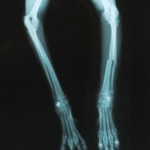

トイプードル 右遠位橈尺骨短斜骨折のALPSによる内固定

当院ではAdvanced Locking plate system(ALPS)と、Locking compression plate system(LCPS)という骨接合法で骨折症例の治療を行っています。

Advanced Locking Plate System

従来型のプレートのように広い面積で骨と接するプレートを用いて固定を行った場合、プレート下の骨はプレートとの接触面において血行が絶たれ壊死し、それがリモデリングされると骨密度が低下する。この骨密度の低下防ぐために、骨折部局所への血行を温存することの重要性が近年改めて認識されるようになってきている。Advaed Locking Plate System (ALPS)は従来型のプレートシステムの欠点を改良し、より使いやすく、より骨への血行を阻害しないようにというコンセプトで作られた。